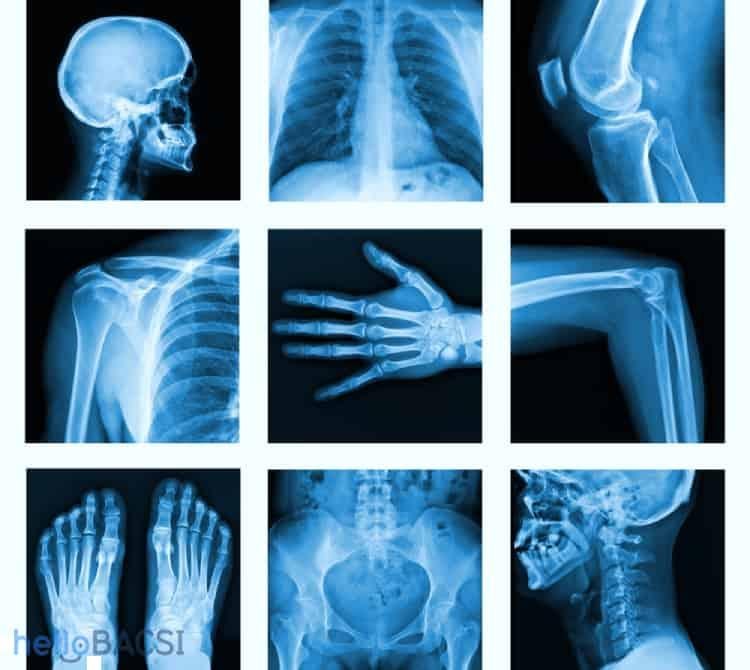

Bác sĩ có thể chỉ định bạn đi chụp X quang để kiểm tra nhiều bộ phận của cơ thể nhằm giúp chẩn đoán hay xác nhận tình trạng sức khỏe, chẳng hạn như:

- Chụp X quang ngực cho thấy tình trạng phổi, dấu hiệu nhiễm trùng, phì đại cơ tim hoặc khối u ở ngực

- Chụp X quang xương để phát hiện gãy xương, loãng xương, nhiễm trùng hoặc khối u

- Chụp X quang vú quan sát sự thay đổi trong mô vú như khối u, ung thư vú

- X quang nha khoa đánh giá răng và hàm

- X quang hệ tiêu hóa giúp phát hiện tắc ruột, hóc dị vật

- Sàng lọc tia X theo thời gian thực (soi huỳnh quang) giúp các bác sĩ đặt ống đỡ động mạch hoặc kiểm tra vị trí của dây dẫn; hoặc chụp động mạch; hoặc để hiển thị đường nét cấu trúc của cơ thể (X quang có thuốc cản quang)

- Chụp cắt lớp vi tính CT cũng là một dạng chụp X-quang, gồm một loạt các tia X chiếu vào một khu vực trên cơ thể để tạo ra hình ảnh 3 chiều (3D).